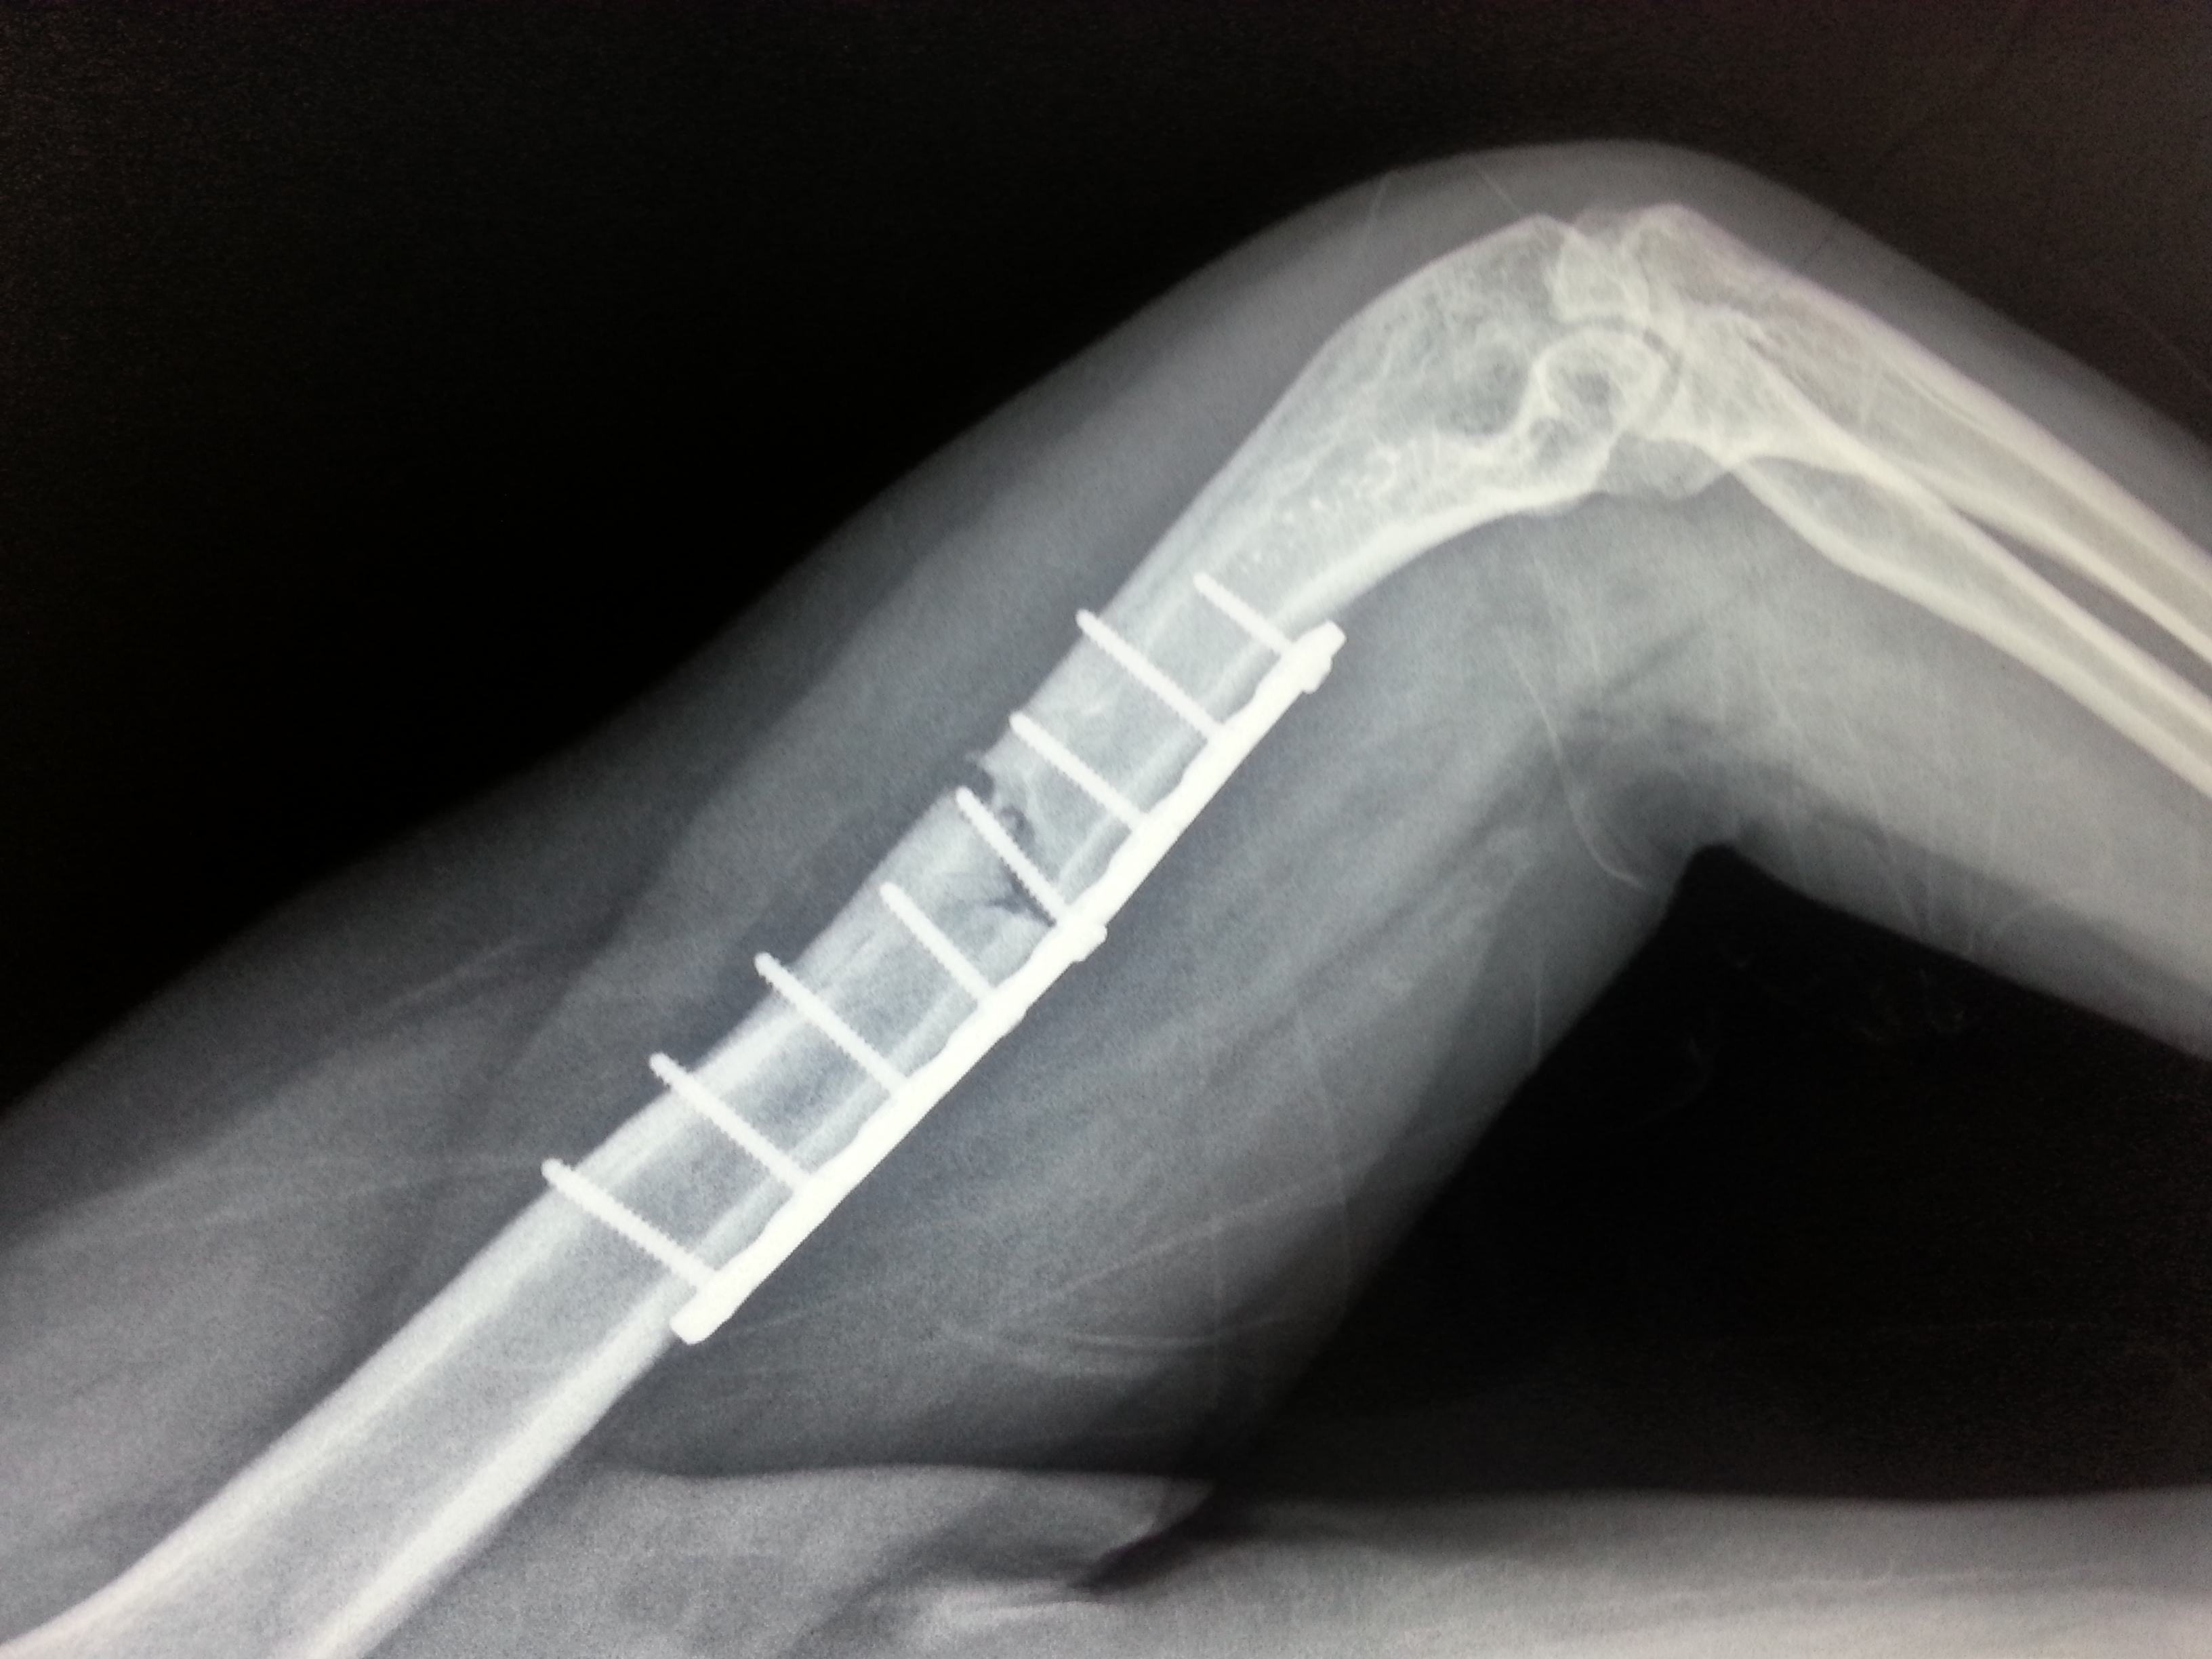

3、如果骨折断的地方还没有接上去

严重影响你的生活质量的话。对于一些简单的骨折移位,医生会选择手法复位,而对于以下手法复位难以取得良好效果的骨折,医生可能会选择通过手术来使你骨折的骨头回到最初的位置上去。而这一类的手术包括钢板螺钉等等这些内固定或者外固定。